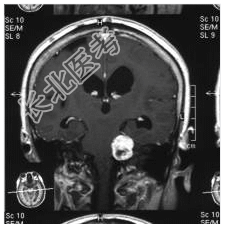

- [材料题] 患者,女性,71岁,因耳鸣、双下肢乏力4~5月,进行性发展入院。体检:左耳听力下降,行走碎步,四肢肌力Ⅴ级,肌张力略高。临床诊断:帕金森综合征。做头颅MRI检查。

- 简答题1、请问该病例诊断是什么?

- 简答题2、请问诊断依据是什么?

- 简答题3、请问鉴别诊断有哪些?

- 简答题4、左听神经鞘瘤的典型症状是什么,以及它是如何影响患者的听力和平衡功能的?

- 简答题5、左听神经鞘瘤治疗措施有哪些?